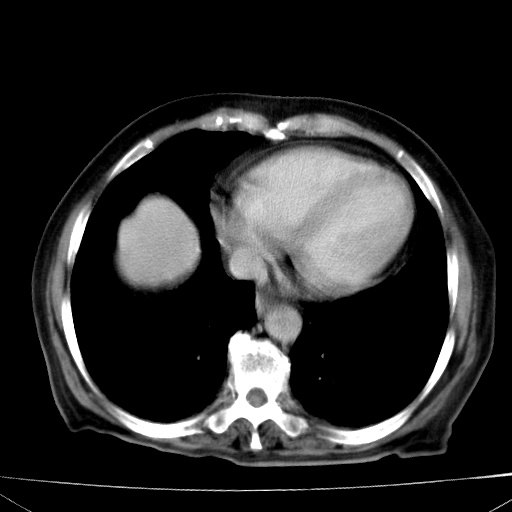

网站人气太旺!昨天的帖子就沉到海底,只好再发贴!ct18338:女 78岁,肝胆病变,已增强,再会诊!原帖链接:http://www.radida.com/bbs/forum.php?mod=viewthread&tid=50032

1)考虑胆囊癌侵犯肝脏并肝门区、腹膜后及右侧膈角后淋巴结转移。2)肝左叶近肝顶部囊肿。3)肝左叶肝内胆管结石。4)左肾近下极囊肿。